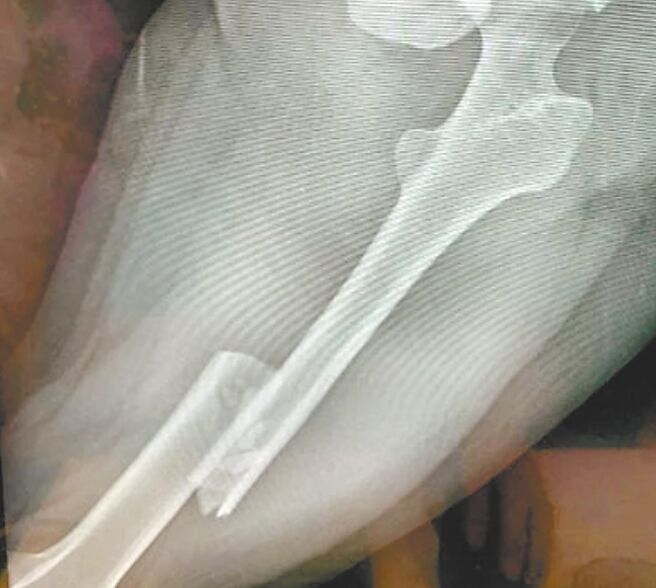

被害人的姊姊透過媒體發文指稱,妹妹覺得和張男交往沒有未來,才在今年4月提議分手。但張男卻認為兩人沒有分手的共識,因此在妹妹返營時開車2度衝撞,造成全身多處骨折,包括顏面受傷、骨盆歪斜、左側股骨骨折,還有第5腰椎骨折,恐怕造成癱瘓。